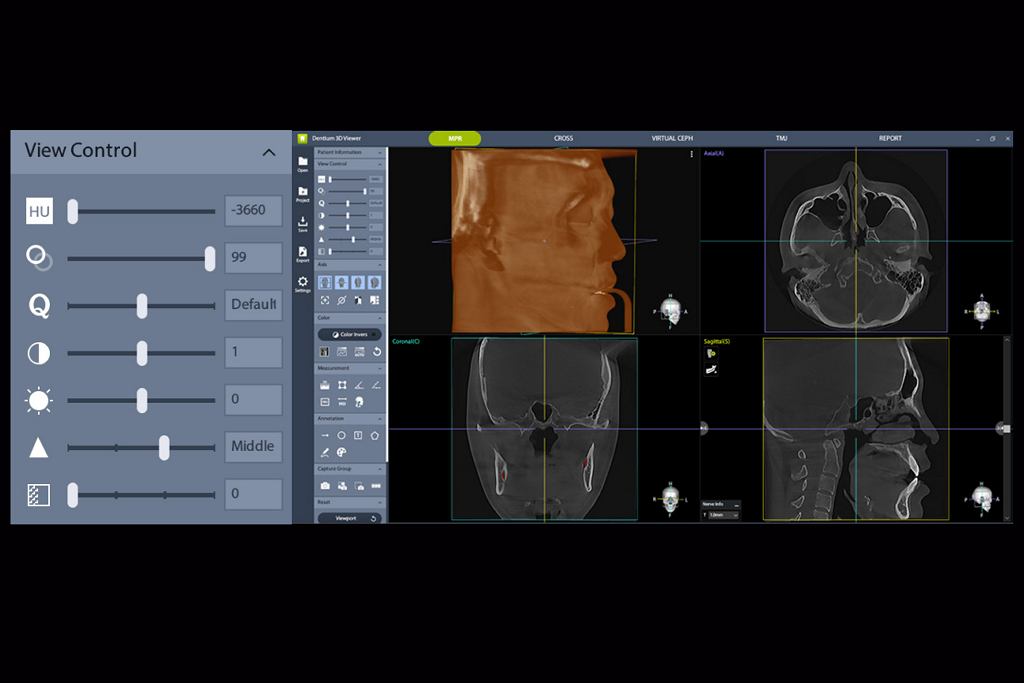

다평면 재구성 (MPR)

한 화면에서 Axial, Coronal, Sagittal 3가지 평면을 동시에 확인할 수 있어 빠르고 직관적인 진단을 지원합니다.

관심 구조물의 축에 맞춰 재구성한 뷰를 통해 비스듬하게 놓인 구조물도 보다 정밀한 분석을 지원합니다.

개선된 뷰어 도구

HU, 투명도, 화질, 대비, 밝기,, 선명도, 노이즈 제거 값을 자유롭게 조절하여 사용자의 보다 편리한 진단을 지원합니다.